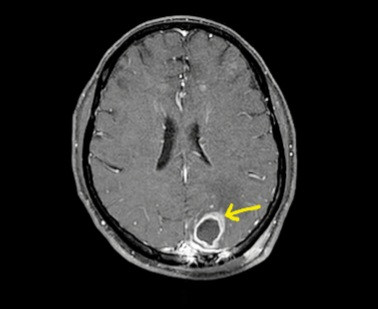

Mới đây, Trung tâm cũng tiếp nhận một ca đặc biệt. Nam bệnh nhân L.D.D, 45 tuổi (Thái Bình), tiền sử đái tháo đường và làm nghề lái tàu trên biển, bệnh nhân được phát hiện có ổ áp-xe trong não; vào viện Trung tâm Thần kinh cấy máu, mủ phát hiện vi khuẩn whitmore, được chuyển sang điều trị tại Trung tâm Bệnh Nhiệt đới.

Sau hơn 20 ngày điều trị kháng sinh và hồi sức tích cực, bệnh nhân đã đỡ sốt, đỡ đau đầu, xét nghiệm ổn định. Tuy nhiên, bệnh nhân cần được điều trị kháng sinh và theo dõi kéo dài ít nhất trong 6 tháng tiếp theo.

![]() |

| Bệnh nhân whitmore bị ép xe não thuỳ chẩm đỉnh trái. |